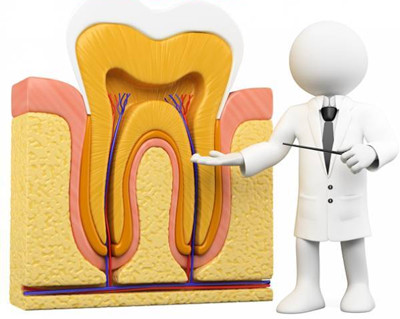

Третмани на коренов канал

Кога ке дојдеме во ситуација да мораме да ја отстраниме пулпата(нервот) таквиот третман се нарекува ендодонција.

Начинот и постапката за одстранување на пулпата од каналот во која што се наоѓа се многу битни, дури и пресудни за иднината на забот.